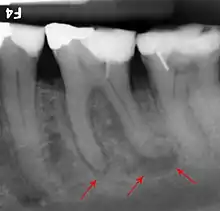

Bone loss in periapical radiograph

2018 Disease Classification of Periodontal Diseases and Conditions breaks down the category of periodontitis into three forms and each of these forms are further broken down into two or more subcategories.[7]